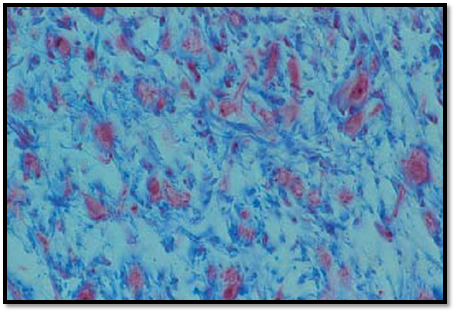

Embryonal Connective T issue—Gelatinous or Mucous Tissue

The embryonal connective tissue (gelatinous tissue, Wharton’s jelly) froma mature human umbilical cord contains connective tissue cells (fibroblasts, fibrocytes) and a homogeneous gelatinous or gel-like ground substance, which holds the collagen fibers. The fibers run in all directions in this space and consequently, they are cut in all planes, across, lengthwise or tangentially. The prevailing ground substances in the gelatinous tissue are amorphous ground substances, which are pre dominantly nonsulfatized glycosaminoglycans.

Stain: azan; magnification: × 400